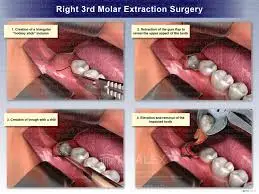

Molar Surgery

Advanced surgical procedure to treat impacted or damaged molars, relieve pain, prevent infection, and restore oral health safely.